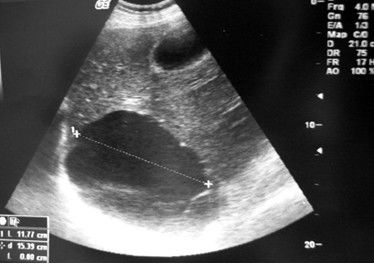

患者信息:男 14岁 山东 潍坊B超成像的基本原理就是:向人体发射一组超声波,按一定的方向进行扫描。

根据监测其回声的延迟时间,强弱就可以判断脏器的距离及性质。

经过电子电路和计算机的处理, 形成了我们今天的B超图像。

基本原理:超声在人体内传播,由于人体各种组织有声学的特性差异,超声波在两种不同组织界面处产生反射、折射、散射、绕射、衰减以及声源与接收器相对运动产生多普勒频移等物理特性。

资料:和普通的声音一样,超声能向一定方向传播,而且可以穿透物体,如果碰到障碍,就会产生回声,不相同的障碍物就会产生不相同的回声,人们通过仪器将这种回声收集并显示在屏幕上,可以用来。

超声探伤和b超的基本原理是一样的,也就是用超声反射来观察内部细节,但是探伤仪是a型,也就是用声波的振幅来表现距离和内部结构,b超是用灰度,也就是明暗对比度的方式显示